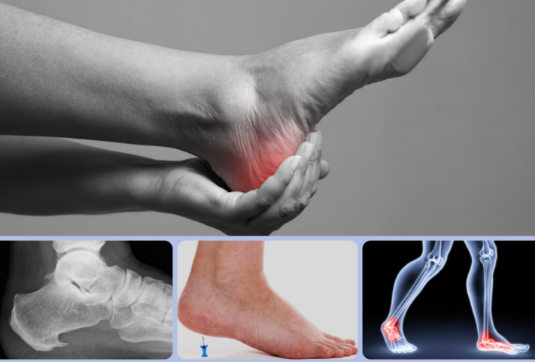

발목 통증은 발목관절에 느껴지는 불편감이나 통증을 말합니다. 경증부터 중증까지 다양하며 갑자기 발생하거나 시간이 지남에 따라 점진적으로 발생할 수 있습니다. 발목 통증은 한쪽 또는 양쪽 발목에 영향을 미칠 수 있으며 다양한 요인에 의해 발생할 수 있습니다.

발목 통증의 일반적인 증상으로는 부종, 압통, 경직, 영향을 받은 발목의 체중 지탱 어려움 등이 있습니다. 구체적인 증상은 근본 원인에 따라 달라질 수 있습니다.

발목 통증을 겪고 있다면 적절한 진단과 통증 완화를 위한 맞춤형 치료 계획을 위해 의료 전문가와 상담하는 것이 중요합니다. 그들은 발목 통증의 근본 원인을 판단하고, 불편함을 완화하고 발목 기능을 복구하기 위한 가장 적절한 치료 옵션을 권장할 수 있습니다.

결론적으로 발목 통증은 다양한 원인에 의해 발생할 수 있지만 각 증상별로 효과적인 해결 방법이 있습니다. 이동성과 삶의 질을 되찾기 위해서는 근본적인 원인을 파악하고 적절한 치료법을 시행하는 것이 중요합니다.